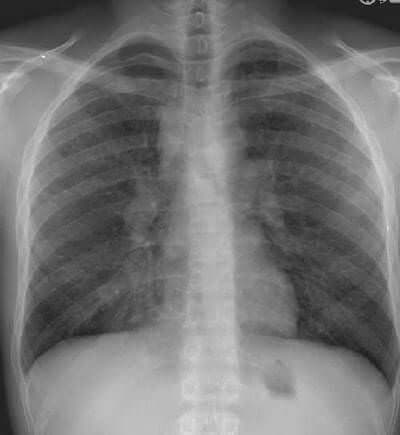

Sarkoidoz Hastalığı Tedavisi

Genetik eğilim yönü olan, müzmin karakterli ve iltihabi türde bir hastalıktır. 100 yılı aşkın bir süredir bilinmektedir. En sık akciğer olmak üzere...